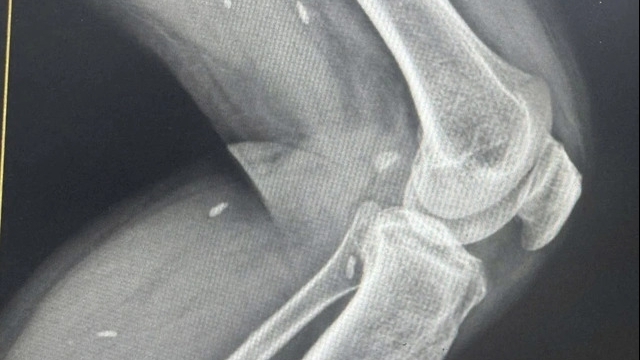

Khoảng 20h ngày 16/10, các bác sĩ đưa bệnh nhân vào phòng mổ. Sau ca mổ hoàn thành thì bệnh nhân phát mê (không mê hoàn toàn, gọi đã biết nhưng còn lơ mơ), bệnh nhân được đưa về phòng hậu phẫu theo dõi. Sau khoảng 10 phút thì bệnh nhân có cơn ngừng thở, các bác sĩ đã tiến hành bóp bóng và xử lý nghiệp vụ, đưa quay lại phòng mổ sau đó đưa về phòng hồi sức tích cực chuyên sâu. Tình trạng bệnh nhân có tiến triển nhưng đến ngày chủ nhật (18/10) thì tình trạng không cải thiện nên người nhà đề nghị chuyển sang Bệnh viện Bạch Mai.

Theo ông Sơn, hiện nay tình trạng bệnh nhân vẫn chưa có cải thiện. Trường hợp của chị Trần Thị Thà là nghi sốc phản vệ, ngộ độc thuốc tê còn nguyên nhân chính xác ra sao thì đến nay bệnh viện cũng chưa thể trả lời báo chí. Người nhà bệnh nhân dùng từ "chết não" là chưa chuẩn bởi "chết não" trong chuyên môn thì điện não đồ phải là một đường thẳng.